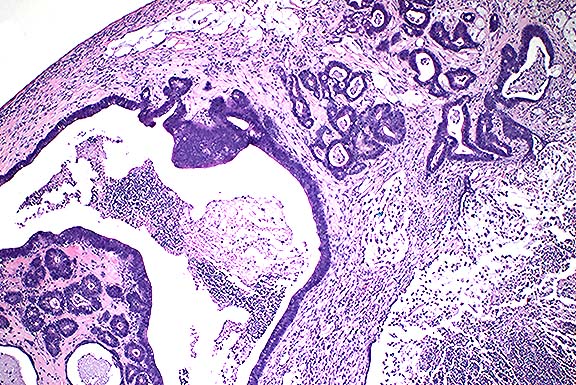

Case IV - Case 2 (AFIP 2594534)

Signalment: Adult, female Sprague-Dawley rat.

History: This rat was sacrificed at the termination of a carcinogenicity study on day 738.

Gross Pathology: The glandular stomach was thickened. Additional gross findings were those commonly seen in aged rats and included tissue masses of the pituitary and liver, mottled adrenals, unilateral ovarian cysts, and unilateral renal distention.

Contributor's Diagnoses and Comments:

1. Stomach: Neuroendocrine cell tumor, malignant.

2. Stomach: Eosinophilic chief cells.

3. Stomach: Fundic hyperplasia.

Neuroendocrine cell tumors of rats have been associated with sustained hypergastrinemia following treatment with gastric antisecretory agents such as omeprazole, but are very rare spontaneously. The present case is an incidental finding and is considered to be malignant due to multifocal invasion of the submucosa. Hypergastrinemia is suggested in this individual by the presence of many eosinophilic chief cells and by the essentially diffuse hyperplasia of the fundus characterized by a slight nodularity of the surface, and increased mucosal thickness due to tortuous distorted glands with increased foveolar:oxyntic gland ratio. Eosinophilic chief cells are rat-specific cells, generally occur multifocally and are reversible. It is of interest that this individual also had a pancreatic islet cell carcinoma; however, it is unknown if the tumor produced gastrin. Pancreatic islet cell tumors are not rare in aged rats, and probably typically do not produce high levels of gastrin since concurrent neuroendocrine cell hyperplasia or tumors are not common.

Case 5-4. Stomach. Demonstrates mucosal neuroendocrine carcinoma invading the submucosa. 20X

AFIP Diagnosis: Stomach: Neuroendocrine carcinoma, Sprague-Dawley rat, rodent.

Conference Note: Conference participants viewed a photograph provided by the contributor which demonstrated positive immunohistochemical staining for neuron-specific enolase in the neoplastic cells. In addition, by immuno-histochemistry performed at the AFIP, the neoplastic cells were positive for synaptophysin. The Churukian-Schenk method demonstrated numerous argyrophilic cytoplasmic granules.

Little is known about the biological activity of gastric neuroendocrine tumors in rats and mice. Metastasis to local lymph nodes has seldom been reported.2 Gastric neuroendocrine tumors are rare in laboratory animals, with the exception of the African rodent Praomys (Mastomys) natalensis, in which gastric carcinoid tumors were reported in two-thirds of males and one-third of females in a closed colony of 600 animals.3,4 In that colony, metastasis was noted in 25% of the cases.3